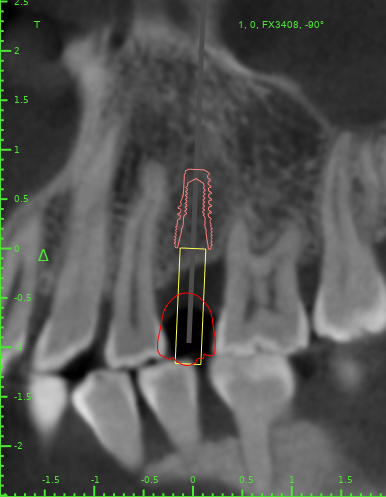

Женька Опубликовано 13 декабря, 2021 Поделиться Опубликовано 13 декабря, 2021 Как считаете, возможно такая позиция имплантата? Ссылка на комментарий

Doc Опубликовано 13 декабря, 2021 Поделиться Опубликовано 13 декабря, 2021 С точки зрения хирурга может и пройдет, а вот ортопед материться будет. Там коронку воткнуть будет нелегко. 1 Ссылка на комментарий

Женька Опубликовано 13 декабря, 2021 Автор Поделиться Опубликовано 13 декабря, 2021 @Doc вот как раз на этот счёт и погляжу пациента в субботу мне тоже кажется, что зуб то не проходит... Что предложили бы такому пациенту, Док? Ссылка на комментарий

Doc Опубликовано 13 декабря, 2021 Поделиться Опубликовано 13 декабря, 2021 1 минуту назад, Женька сказал: @Doc вот как раз на этот счёт и погляжу пациента в субботу мне тоже кажется, что зуб то не проходит... Что предложили бы такому пациенту, Док? Ну, тут прикуса толком не видно, поэтому сложно сказать. Но в такой ситуации либо ортодонтия, либо будет узкая страшненькая короночка с большими поднутрениями для хранения пищи. Ссылка на комментарий